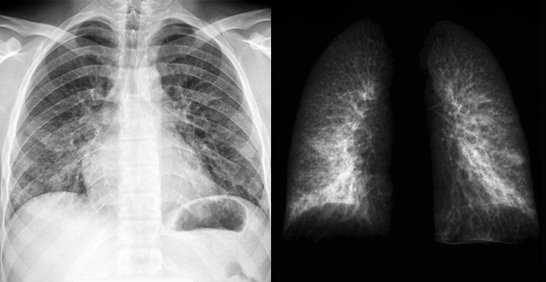

폐암 초기증상 6. 가슴 통증

기침과 함께 흉통이 동반되는 상황을 대부분으로 많은 폐암환자들이 겪고 있는 증상입니다. 그리고 기침과 함께 동반하는 흉통이 있다고 하면 폐 엑스레이를 찍어봐야 하고, 가슴의 통증 및 흉통이 발생하는 이유는 흉막과 흉벽에 위치한 암 때문으로 보통 따끔거리는 증상이나 날카로운 것으로 찌르는 듯한 가슴통증이 있습니다. 이러한 폐암 초기증상이 있다면 참지 말고 즉시 내원하여 진찰받아 보시기 바랍니다.